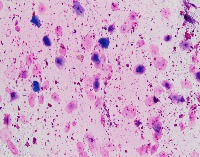

Medical Image Analysis: geckler3 could be used by healthcare professionals, researchers, and medical students to quickly and accurately identify White Blood Cells (WBC) and Erythrocyte-Hemoglobin Concentration (EHC) in clinical images, improving diagnosis and understanding of various blood-related conditions and diseases.

Blood Disorder Diagnosis Support: Implement geckler3 in diagnostic tools to assist doctors in identifying blood disorders, such as anemia or leukemia, by accurately analyzing WBC and EHC levels in blood images, helping with faster and precise diagnosis and treatment.

Biomedical Research: Utilize geckler3 in research laboratories for various biomedical and biotechnological studies to analyze large datasets of blood images, streamlining the process of data collection and analysis by automatically detecting WBC and EHC patterns.

Training and Educational Tool: Integrate geckler3 into educational platforms or applications to help medical and laboratory professionals, as well as medical students, learn and practice the identification of WBC and EHC in blood images, enhancing their skills and knowledge.

Remote Diagnosis Assistance: Employ geckler3 in telemedicine applications, allowing healthcare professionals to remotely access and analyze blood images for the presence of WBC and EHC, aiding in the diagnosis and management of blood-related conditions in areas with limited medical facilities.